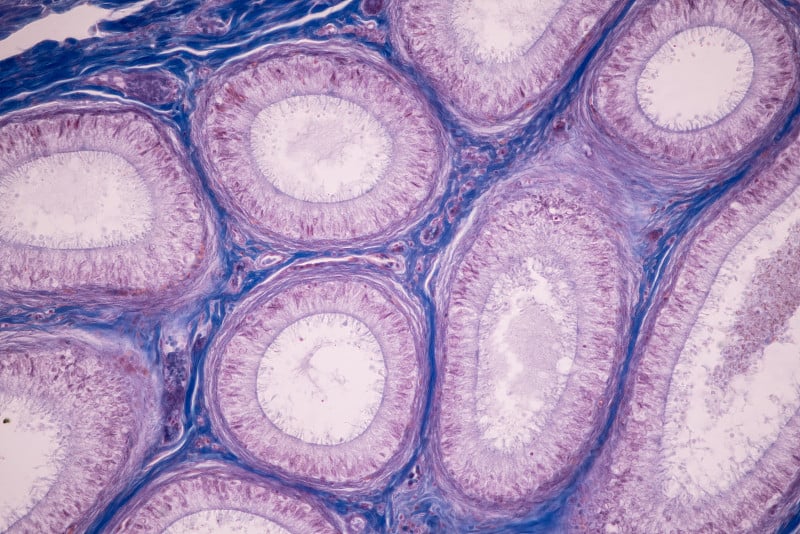

睾丸,男性的性器官详情

EPS